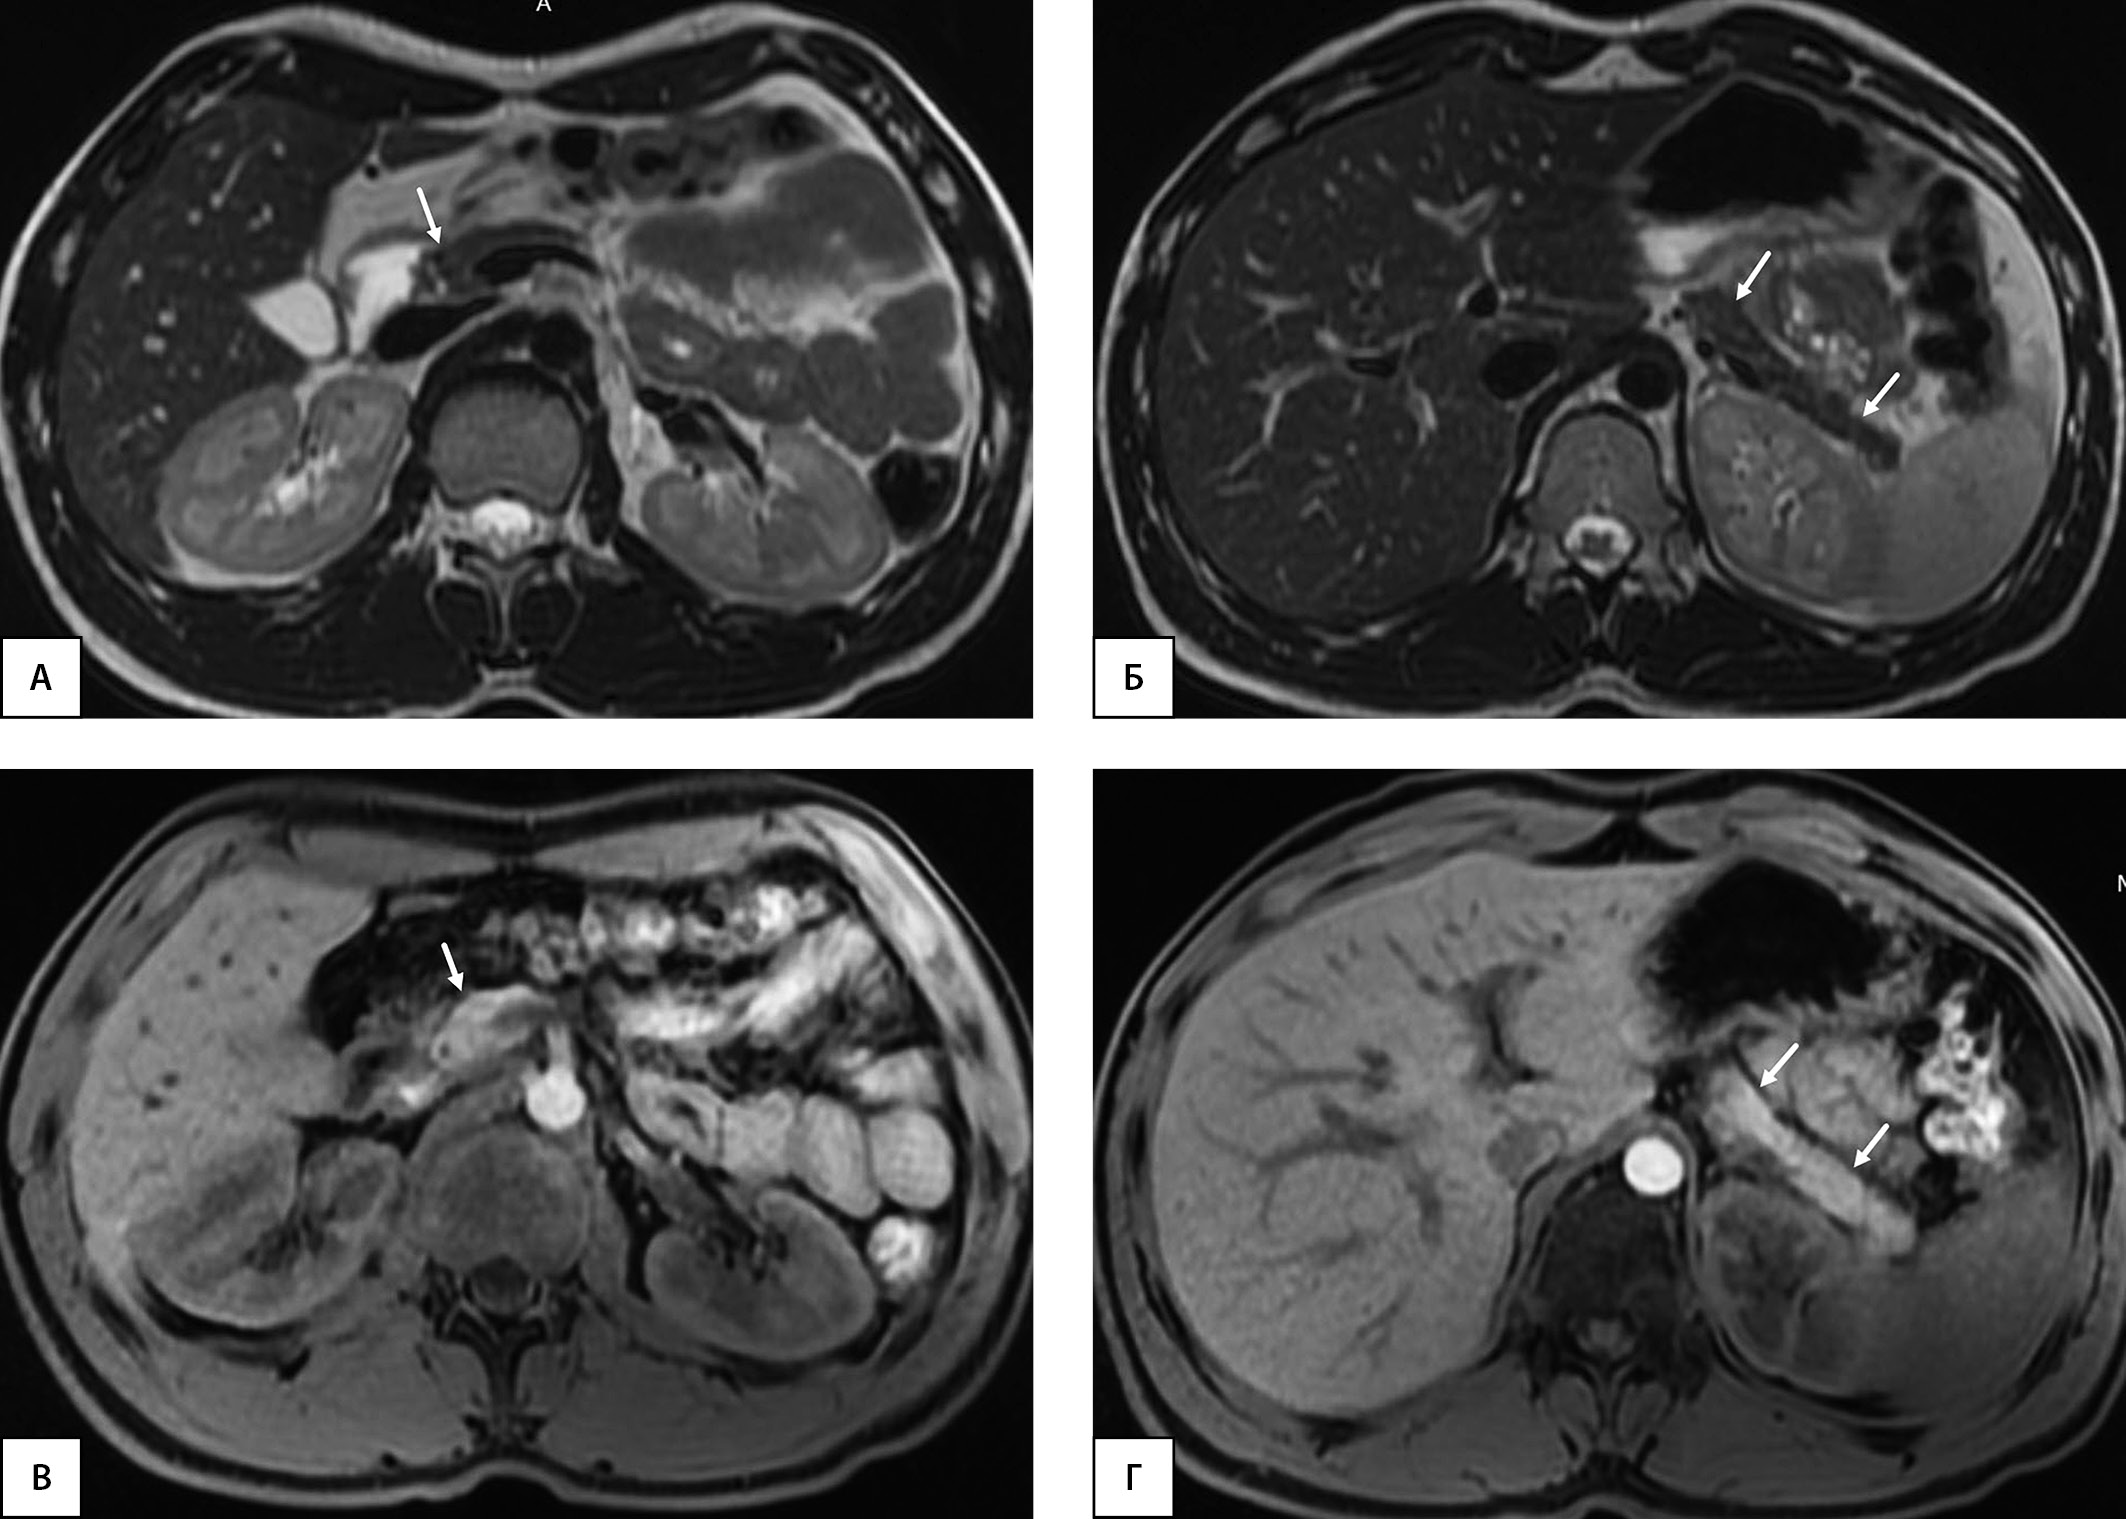

Рисунок 2. Здоровый доброволец из группы контроля, 25 лет, без нарушений углеводного обмена. МРТ органов брюшной полости на уровне головки поджелудочной железы (А) и на уровне тела и хвоста (Б) (поджелудочная железа показана стрелками). А и Б — Т1-ВИ, аксиальная плоскость. ОПЖ=57,3 мл; ОПЖ/ИМТ=57,3/24,3=2,36 мл/(кг/м2); ОПЖ/ППТ=57,3/1,98=28,93 мл/м2.

Примечание. ОПЖ - объем поджелудочной железы. ИМТ - индекс массы тела. ППТ - площадь поверхности тела. ВИ - взвешенные изображения.